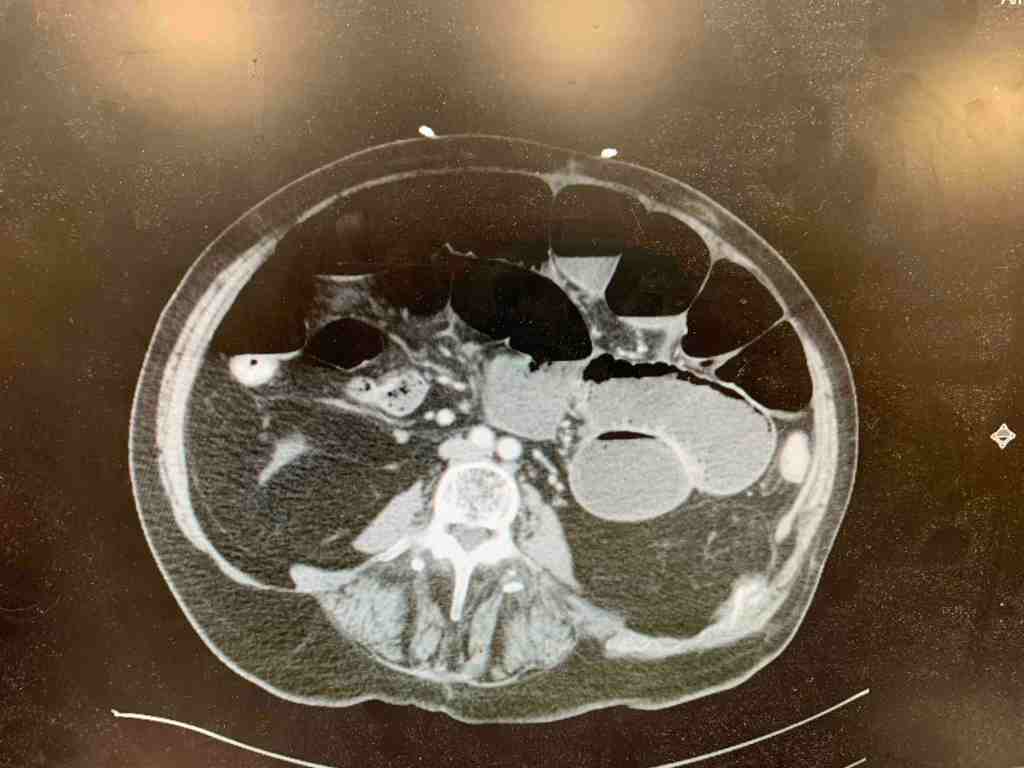

CT was obtained:

CT showed dilated loops of bowel with air fluid levels confirming the diagnosis of SBO. Surgery was consulted and the patient was admitted for further care.